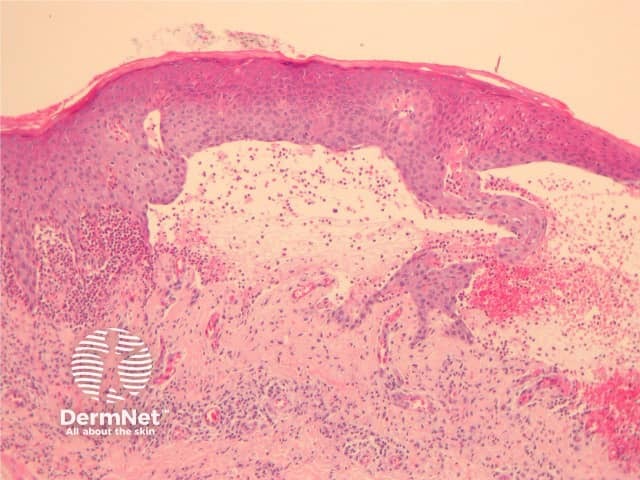

Early lesions during the urticarial phase may be non-specific and show mild upper dermal oedema with perivascular infiltrate (figure 1). There are often conspicuous eosinophils. Immunofluorescence is very helpful in this early phase.

Established blister: The blister is subepidermal and contains fibrin and large numbers of inflammatory cells including eosinophils (figures 2, 3). The eosinophils may be very dense in areas and form small abscesses in the superficial dermis.

Figure 1

Figure 2